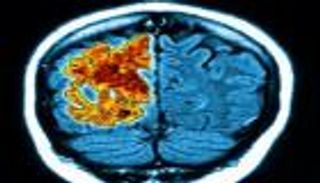

باحثون في إمارة الشارقة نجحوا في الوصول إلى مركبات كيميائية يمكن أن تكافح الخلايا المسؤولة عن الإصابة بمرض ألزهايمر وسرطان الثدي.

نجح باحثون في معهد الشارقة للبحوث الطبية والصحية وأكاديمية الشارقة للبحوث العلمية في الوصول إلى مركبات كيميائية يمكن أن تكافح الخلايا المسؤولة عن الإصابة بمرض ألزهايمر وسرطان الثدي.

وأشار الدكتور طالب التل مدير المعهد والأستاذ في كلية الصيدلة بجامعة الشارقة إلى أن دراستين منفصلتين أجراهما المعهد والأكاديمية على مدى 3 سنوات سابقة، توصلتا إلى 15 مركبا يمكنها محاربة الخلايا التي تسبب مرض ألزهايمر، إضافة إلى 3 مركبات يمكنها مكافحة الخلايا المسؤولة عن تطور سرطان الثدي، لافتا إلى أن نتائج الدراستين نشرت في مجلات طبية عالمية بما في ذلك المجلة الأمريكية للكيمياء الطبية.